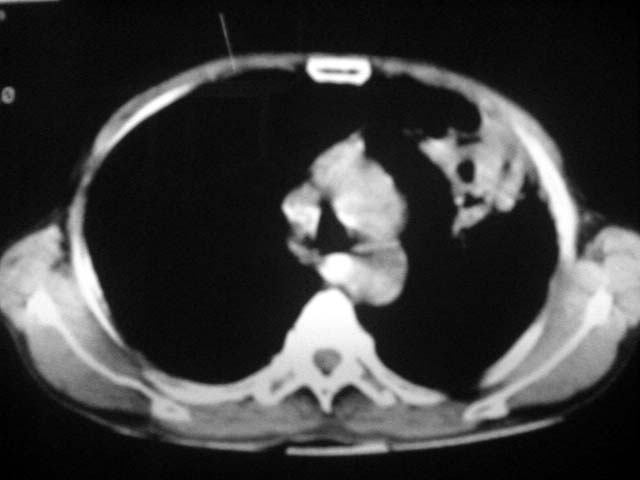

以下是引用zjzjr在2007-9-4 17:00:00的发言:[br]双上肺继发型结核伴左上肺空洞形成.慢性支气管炎伴肺气肿.

以下是引用liuzheng_9326在2007-9-4 16:23:00的发言:[br]痰检未见结核菌, 治疗后症状好转。图像符合陈旧性结核伴感染。